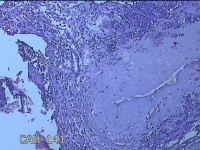

子宫腔妊娠残留物

性别

女

年龄

39岁

临床诊断

早期人工流产术后 疤痕子宫 不全流产?

一般病史

停经11周。

标本名称

大体所见

灰白暗红色不规则碎组织4x3.5x0.8cm一堆,未发现明显的绒毛样组织。